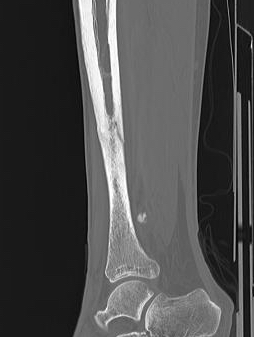

Xray

Cortical thickening

Look for "dreaded black line" - sign of fracture

Periosteal thickening with possible "dreaded black line"

Anterior cortical thickening with dreaded black line

CT